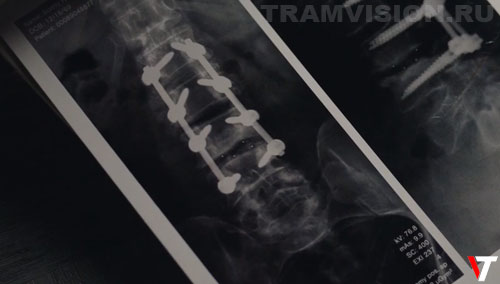

Шея у Сонни находится в заднице! Когда Рубен показывает ему рентгеновские снимки и читает медицинское заключение "перелом пятого шейного позвонка...", на снимке виден таз, т.е. это поясничный отдел.